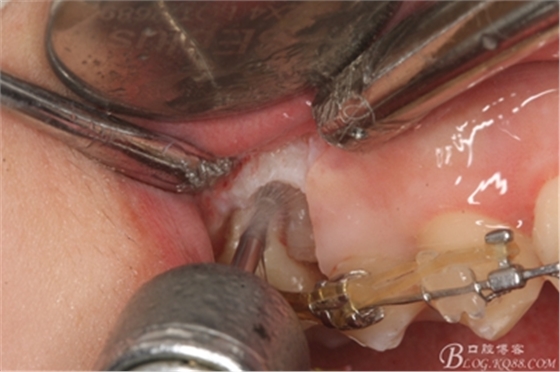

圖14.用小球鉆縱分15牙根

圖15 .微創(chuàng)挺把15牙根縱分成近遠中兩塊

圖16.微創(chuàng)挺挺松近中根面部分,從16與14之間間隙出來

圖17.血管鉗取出近中部分15牙根